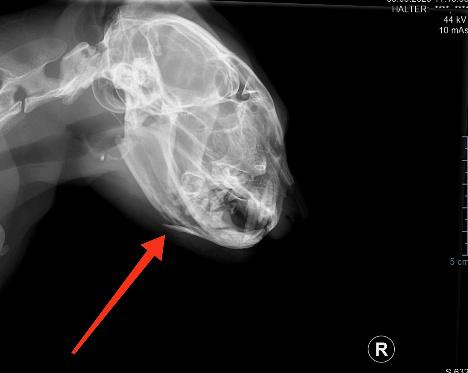

Der angefahrene Kater wurde um zwölf Uhr nachts in die Tierarztpraxis Ilztal VET versorgt.

Durch das digitale Röntgengerät sieht man deutlich, dass nur ein Teil des Unterkieferknochens abgespalten ist. Die offene Verletzung wurde genäht und muss regelmäßig versorgt werden.